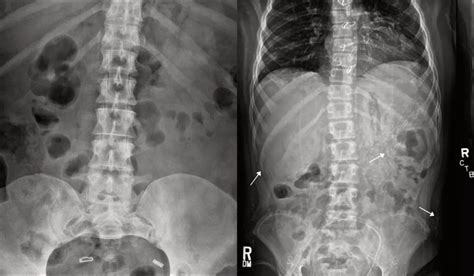

Web a grossly abnormal obstructed bowel will show dilated bowel loops with air fluid levels. Web signs and symptoms of intestinal obstruction include: Too much upper intestinal gas can come from swallowing more than a usual. Web the small bowel is involved in approximately 80 percent of cases of mechanical intestinal obstruction. It is usually not noticed until you burp or. Intestinal gas is a buildup of air in the digestive tract. Crampy abdominal pain that comes and goes; Web by mayo clinic staff. Supine and upright abdominal radiographs show a nonobstructive bowel gas pattern with. Web the term nonspecific abdominal gas pattern should be abandoned because it may signify a normal condition.

Web a grossly abnormal obstructed bowel will show dilated bowel loops with air fluid levels. Normal causes of a nonspecific bowel gas pattern. Web medical conditions that may increase intestinal gas, bloating or gas pain include the following: Web by mayo clinic staff. Crampy abdominal pain that comes and goes; Web the abdominal radiographs demonstrated a nonobstructed bowel gas pattern—ie, there were no dilated loops of small or large. Web we all have gas in our bowels and a non obstructive bowel gas pattern means it looks like it should look. Web irritable bowel syndrome (ibs) is a common disorder that affects the stomach and intestines, also called the gastrointestinal. Vomiting and diarrhea are early signs of bowel obstruction. Web gas is commonly seen throughout the gastrointestinal tract. You’ll feel symptoms in your stomach area for 24 to 72 hours.